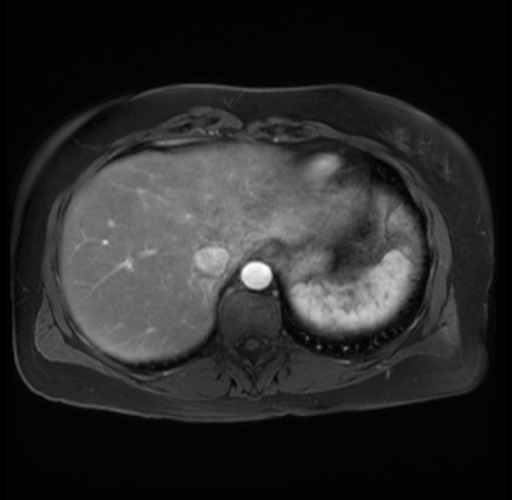

Imaging Analysis

Look through the patient's CT scan to identify any areas of concern for the necessary procedure.

Based on your CT findings, which issue(s) are present and would give reason for "planned slowing down moment(s)" in this case?